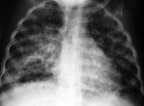

La tuberculosis farmacorresistente alcanza niveles sin precedentes a nivel mundial

En algunas zonas del mundo alrededor del 25% de las personas con tuberculosis padece una forma de la enfermedad que no responde a los tratamientos convencionales. Asia es el continente con más afectados.